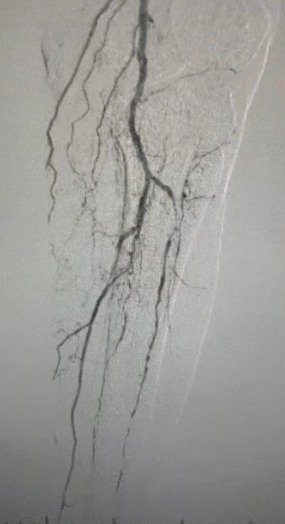

· Imagem pré-operatória: estenose calcificada difusa grave em artérias bilaterais dos membros inferiores

Resultado cirúrgico

Pós-procedimento, a estenose arterial melhorou significativamente, o fluxo sanguíneo aumentou e a temperatura da pele aumentou. Nenhuma complicação pós-operatória ocorreu. Tanto o paciente quanto a equipe cirúrgica ficaram muito satisfeitos com os resultados.